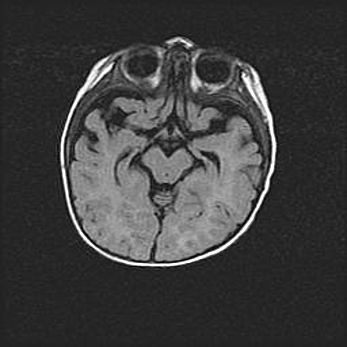

Лейкомаляция с кистозно-глиозной дегенерацией головного мозга.

Возраст: 2 месяца 25 дней

Вес: 6400 г

Окружность головы: 40 см

Срок гестации: 41 неделя

Лейкомаляцию относят к ишемически-гипоксическим повреждениям головного мозга, диагностируемым у новорожденных. При лейкомаляции в головном мозге обнаруживают очаги некроза, возникшие после тяжелой гипоксии и нарушения кровотока. В процессе морфогенеза очаги проходят три стадии: 1) развития некроза, 2) резорбции и 3) формирования глиозного рубца или кисты. Перивентрикулярная лейкомаляция (ПЛ) встречается примерно в 12% случаев среди новорожденных, обычно – у недоношенных детей, причем, частота ее зависит от массы, с которой младенец появился на свет. Наибольшее число малышей страдает лейкомаляцией, если масса при рождении 1500-2500 г.